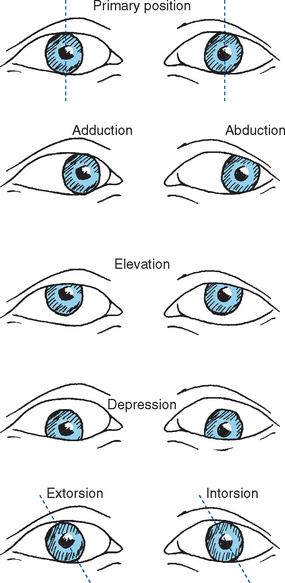

Abduction And Adduction Eyes

ladybird.beauty

ladybird.beauty

oblique rectus movements extraocular movement nerve adduction abduction tms ocular temporal trochlear depression